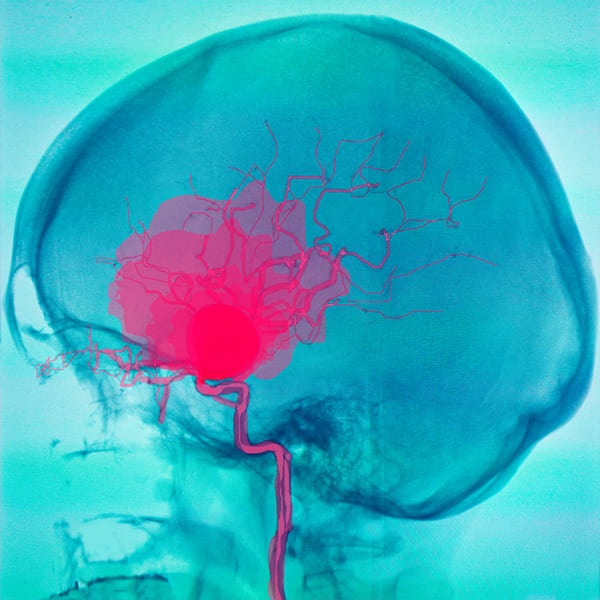

Cirugía aneurisma cerebral

Reparación de la zona débil en la pared de un vaso sanguíneo.

Cirugía craneal

Intervención que trata problemas en el cerebro o las estructuras circundantes. Puede ser necesaria para intervenir un tumor, por sangrado por traumatismos, problemas de los vasos sanguíneos, infecciones en el cerebro, presión craneal, y ciertas enfermedades como la epilepsia o el párkinson.